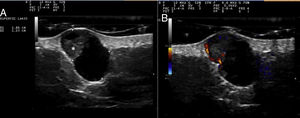

Cutaneous ultrasound (12-18MHz) revealed an oval, well-defined dermal-hypodermal structure measuring 1.85×1.23cm. This lesion was cystic in appearance, with an anechoic interior and posterior enhancement. A triangular hyperechogenic area protruding through the wall was clearly visible in the upper pole (Fig. 2A). Color Doppler mode revealed increased peripheral vascularization, especially in the triangular solid portion (Fig. 2B).